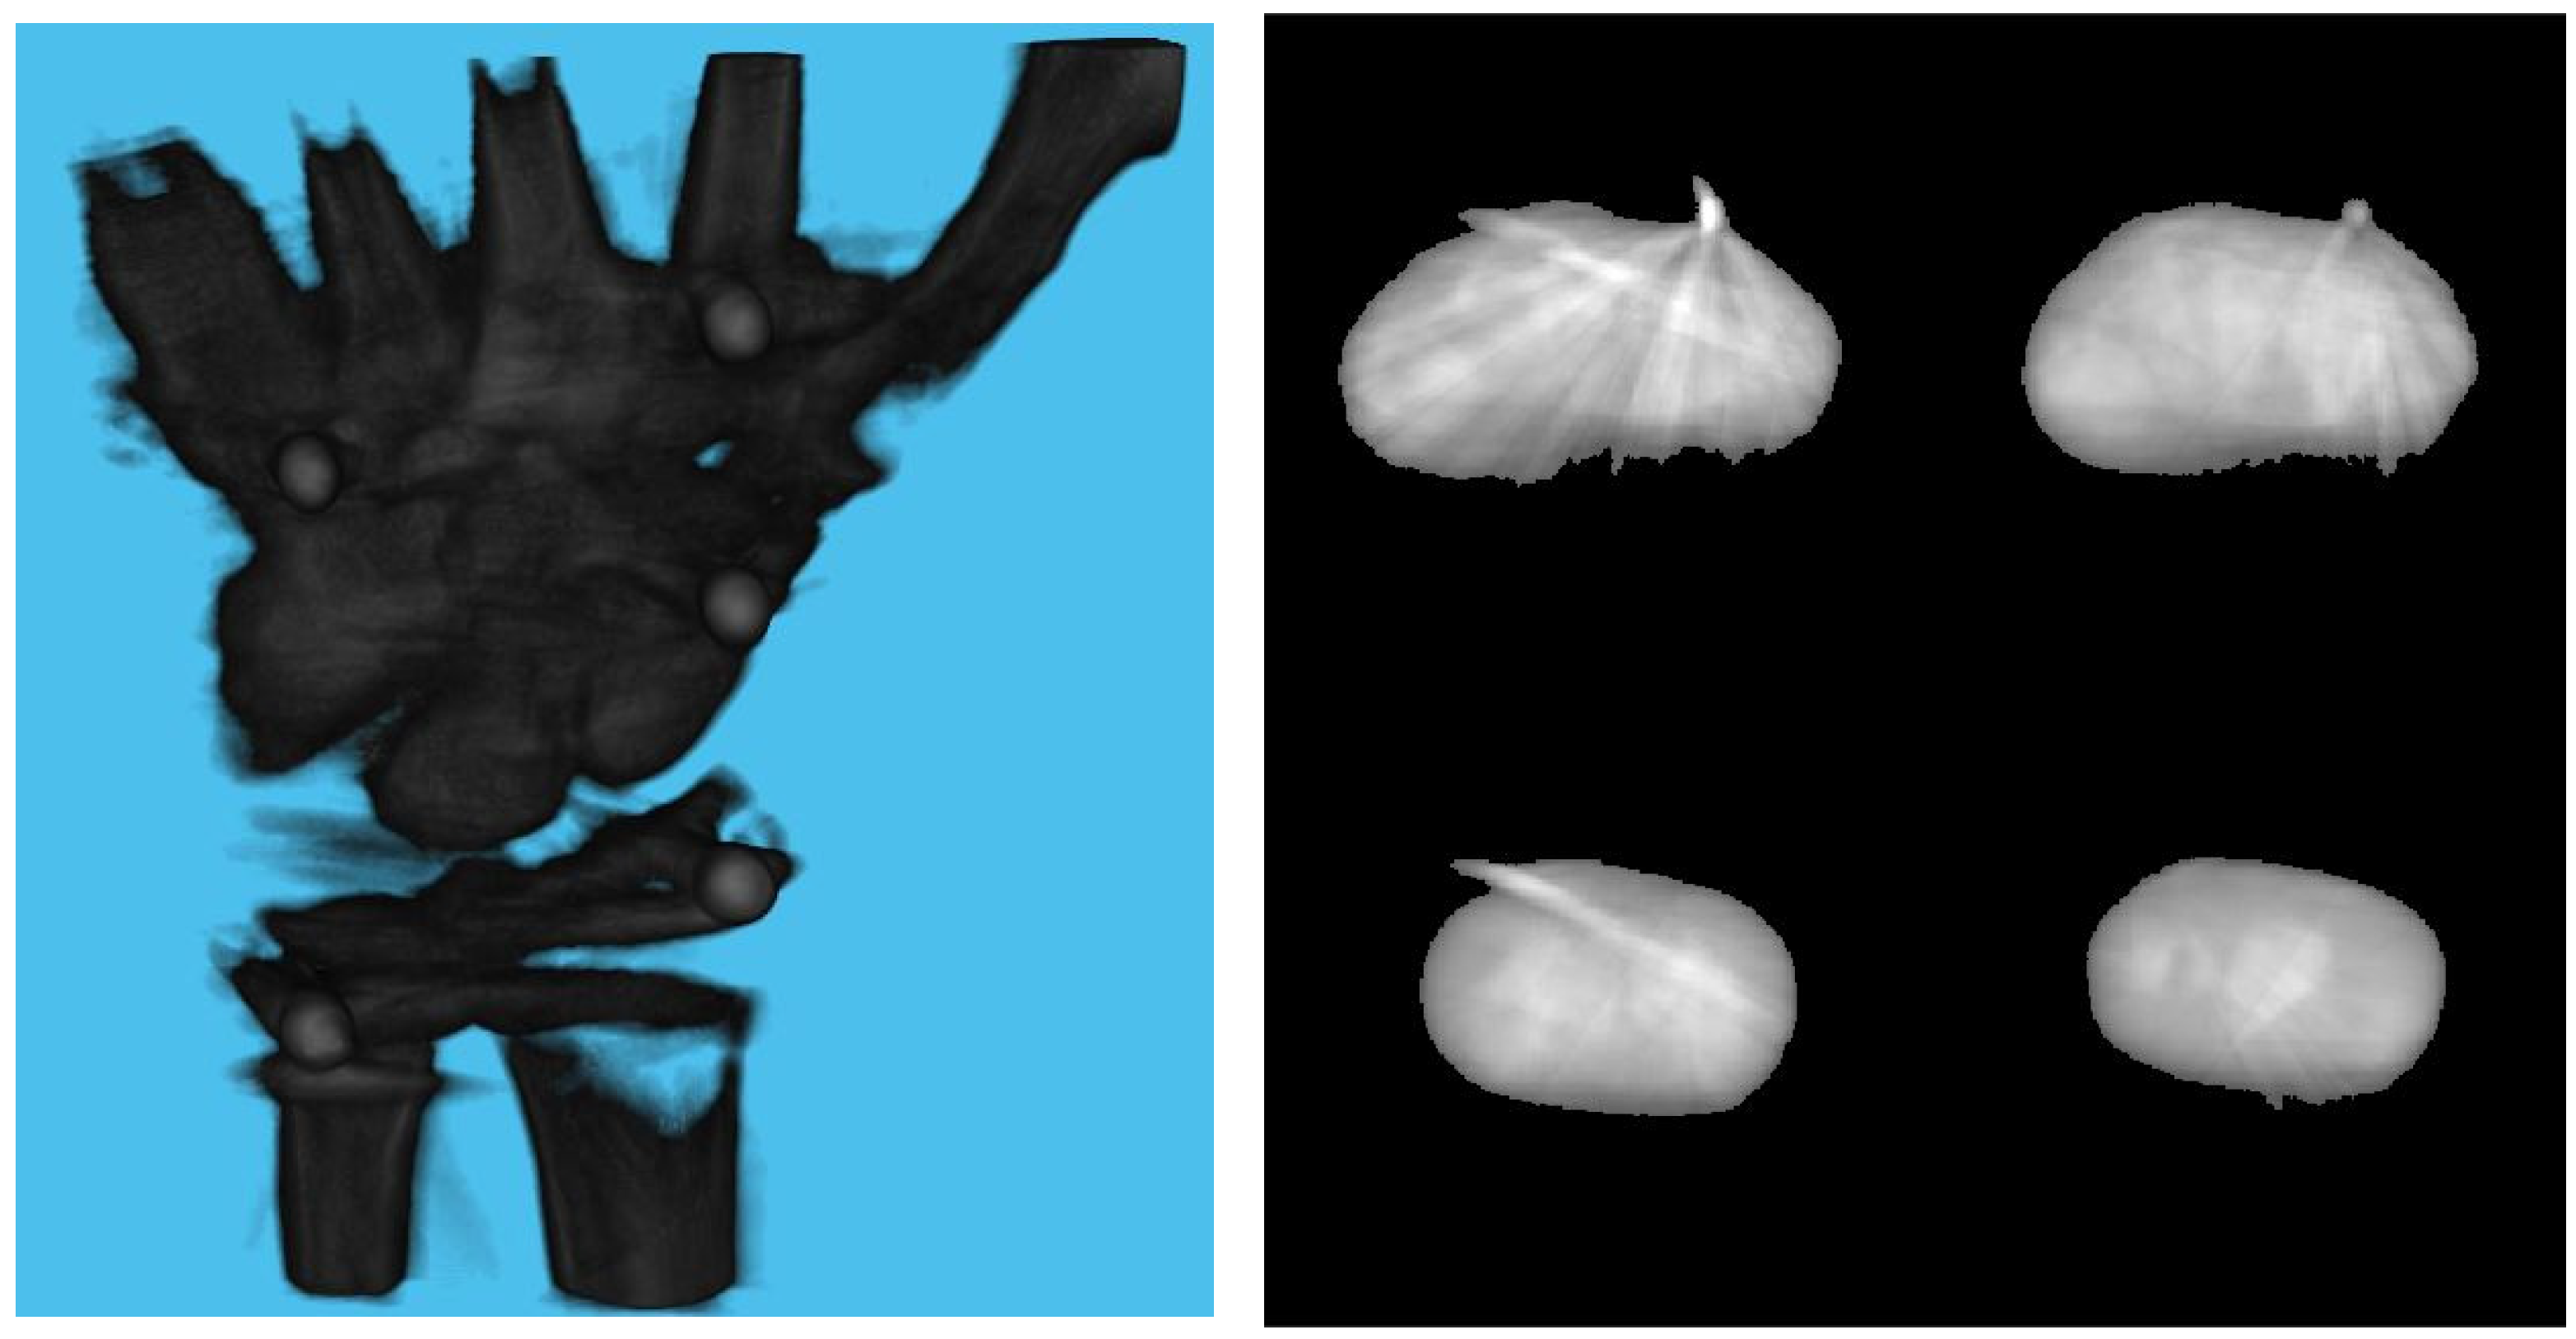

3. Experiments and Results

3.1. Simulation Setup

3.2. Effect of Board Thicknesses and Marker Sizes on Reconstructed Image Quality